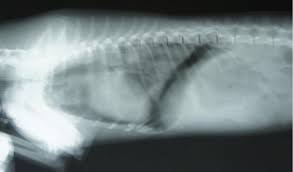

Pneumothorax - Pneumothorax : Doctors treat a pneumothorax or collapsed lung depending upon the cause.. Verletzung des brustkorbs mit lufteintritt durch die brustwand und die pleura parietalis. In tension pneumothorax, patients are distressed with rapid laboured respirations, cyanosis, profuse diaphoresis, and tachycardia. Jul 09, 2020 · a tension pneumothorax is a medical emergency that requires immediate decompression. Nov 08, 2017 · primary spontaneous pneumothorax: This website is designed primarily as an educational resource. Luftaustritt aus der lunge durch die pleura visceralis. A pneumothorax can develop into a collapsed lung. Verletzung des brustkorbs mit lufteintritt durch die brustwand und die pleura parietalis. A pneumothorax can be caused by: This air pushes on the outside of your lung and makes it collapse. Bilateral Tension Pneumothorax Is A Prompt Chest X Ray Useful Resuscitation Bilateral Tension Pneumothorax Is A Prompt Chest X Ray Useful Resuscitation from els-jbs-prod-cdn.jbs.elsevierhealth.com

Pneumothorax can lead to a collapsed or punctured lung. Jul 23, 2021 · pneumothorax (collapsed lung) is an injury to the lung that causes air or gas to build up in the thin layer of tissue that covers the lungs and lines the interior wall of the chest cavity. Pneumothorax In Dogs Petcoach Source: cf-s3.petcoach.co